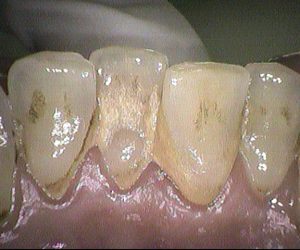

今日のクリーニングです。 クリーニング前 この方は約3年ぶりのクリーニングで、 下の前歯の間から根元にかけて歯石が多くついていました。 クリーニング後 […]

今日のクリーニングです🦷 下の前歯の表側、裏側のクリーニング前後のお写真です📸 歯と歯の間や歯ぐきのきわには歯石が付着していて、 歯の表面にはステイン(着色)が […]

今日のクリーニングです🦷 歯科医院は30年以上ぶりだという患者さんです。 下の前歯の表側と裏側のクリーニング前後のお写真です📸 歯と歯の間や、歯ぐきのきわには歯石が多く付 […]

今日のクリーニングです🦷 歯科医院は5年ぶりの患者さんです 下の前歯の表側、裏側のクリーニング前後のお写真です📷 歯と歯の間には歯石が付着しており、表面にはすこ […]